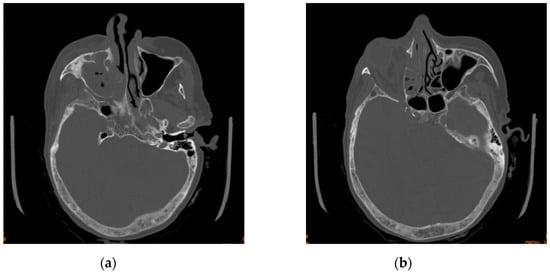

The head CT revealed right-sided orbital abscess with reticulation of the fat, pansinusitis with maxillary and ethmoid sinus opacification (Figure 2), multiple gas bubbles extending from the ethmoidal cells to the right orbit, a stretched right optic nerve, and posterior globe tenting (Figure 3). The abscess in the right canine space originated from the buccal roots of teeth 13 and 15. The fluid collection extended continuously from the right canine space upward and backward to the right lateral orbit.

Figure 2. Axial section of computed tomography scan displaying (a) maxillary sinus opacification and (b) ethmoid sinus opacification.